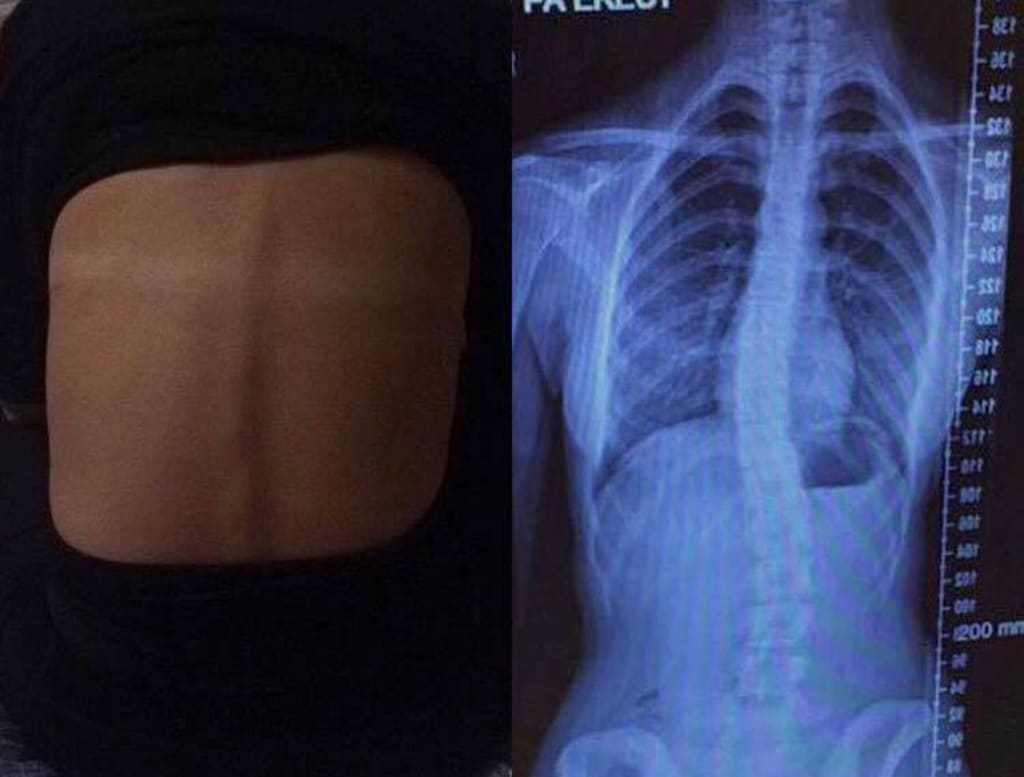

Then it brings us to November 2016 in London where they diagnosed me with "Acute Scoliosis," an S-shaped back. Commonly it does not cause pain… I had to be the anomaly didn’t I hahaha. Yes, it may be slight. Yes, there are people who have a more extreme angle of bend. Yes, the scoliosis I have isn’t bad enough to have an operation. However, it is still there. I still get pain. It still restricted me from dancing—which is a big factor in my life.

A lot of “if’s and but’s” however, we’re getting there… It goes to show the more you press for answers and not give up you soon will get on the track to find out the causes of these slight or big problems. Here is a simple sum up of scoliosis: The majority of cases have no identifiable cause—this is called idiopathic scoliosis. It is an extremely common spinal deformity. Scoliosis is diagnosed both males and females, however, females are significantly more likely to have scoliosis curves that progress and need either bracing, physiotherapy, and/or surgery . Early diagnosis is extremely important .

Google explanation: Abnormal lateral curvature of the spine . What do you do if you think you have or your child has scoliosis? You need to make an appointment with your doctor ASAP. If the first examination shows some abnormalities the doctor usually will order an X-ray and/or MRI scan to be done so he/she can assess the degree of the curve and the steps to do next. It is possible for untreated scoliosis to progress and lead to more serious complications (which is not what we want!), such as the potential for chronic pain and/or restricted activity. To prevent further complications for scoliosis, treatment and early detection is a must!